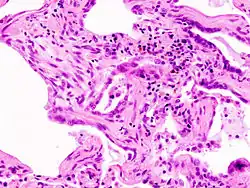

| Micrograph of usual interstitial pneumonia (UIP). UIP is the most common pattern of idiopathic interstitial pneumonia and usually represents idiopathic pulmonary fibrosis. H&E stain. Autopsy specimen. | |

Usual interstitial pneumonia is the most common type.[8]